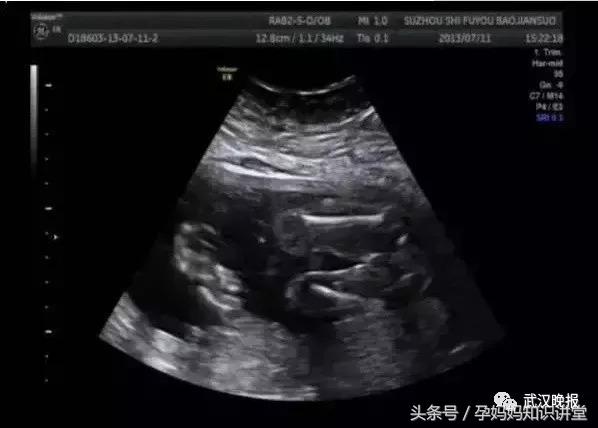

但不少准妈妈看后觉得很“狗血”:怀上双胞胎,怎会突然变一个,还能顺利生产?对此,产科专家表示,双胎变单胎的情况确实可能出现。

有的准妈妈刚查出怀孕时是双胎,但到了12周B超发现只是单胎,也有在孕中晚期的双胎准妈妈,有一个宝宝突然出现问题保不住了。

一般来说,孕早期消失的胎儿,常常被胎盘或母体吸收,剩下的胚胎可正常发育,母亲基本不会有不适。接近孕中期胎儿,由于受到另一正常妊娠胎儿的挤压,到母亲分娩时,这个死胎就变得又扁又薄,被称为“纸样儿”,一般在分娩后处理。这两种情况都属于“自然减胎”,原因复杂,可能是自然界优胜劣汰的表现,大多发生在双绒毛膜性的双胎(双卵双胎)和试管婴儿上。